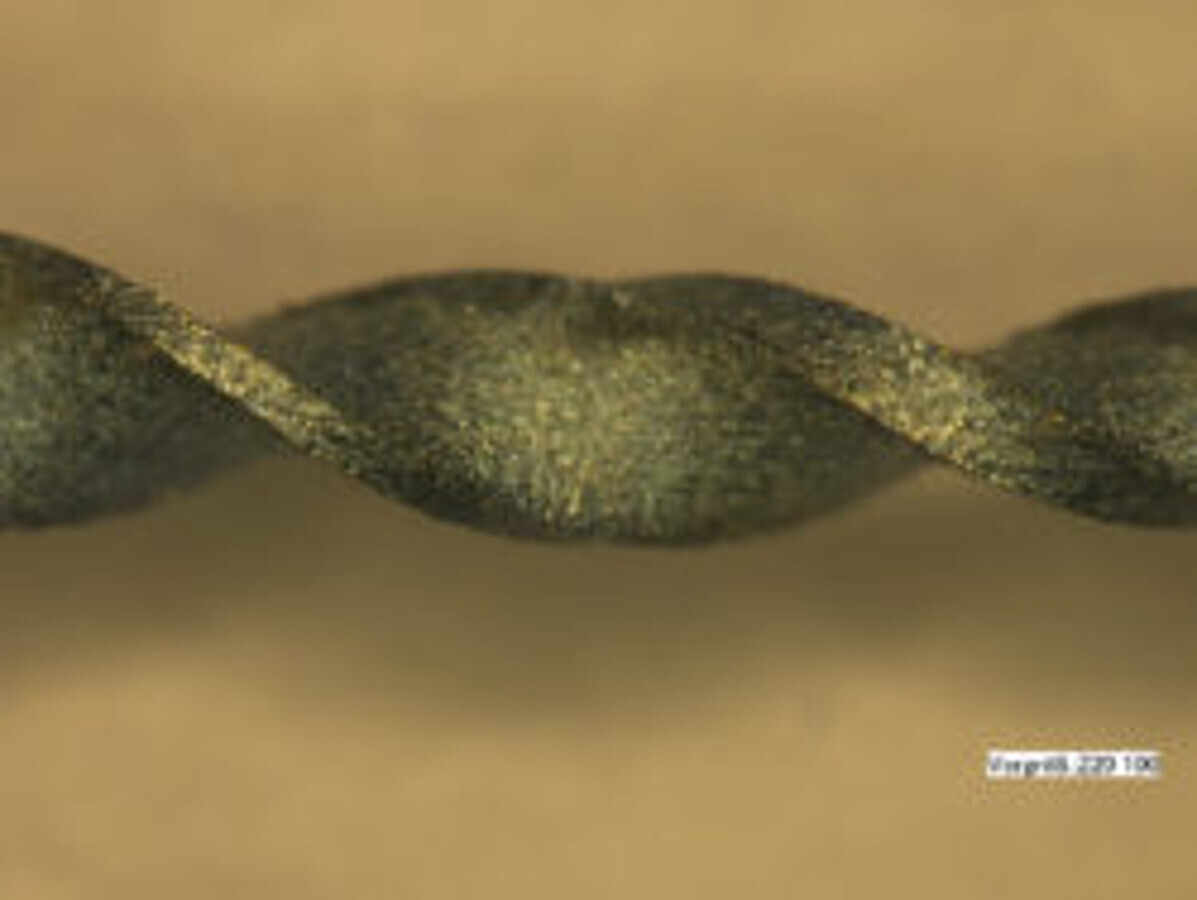

Another feature of the file system used in this case is the controlled memory (CM) effect. NiTi files with this CM effect can be pre-bent in a similar manner to classical stainless-steel files and remain reliably in this pre-bent form even after insertion into the canal. If the distal molars are difficult to access or if the root canals are unusually curved, such a feature of the otherwise extremely flexible file may well prove helpful (Figs. 3 & 4). In addition, the file moves safely in the centre of the canal and adapts to the natural profile of the canal. This avoids any straightening, zipping or similar unwanted effects. The risk of causing iatrogenic damage cannot be neglected if the procedure is too invasive, particularly in the case of challenging anatomical conditions.

Fig. 3: Pre-bendable NiTi file.

Fig. 4: NiTi file in pre-bent condition.